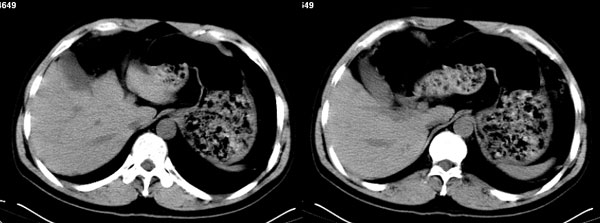

影像学表现:1 腹腔前中部、胰腺前方囊实性病灶(个人认为确定有否实性成分存在这是关键,涉及到鉴别诊断,如果是口服阳性造影剂则可明确左侧是不是小肠了),囊性部分囊壁不均,实性部分有强化,与小肠关系较密切,局部小肠受推移;与胰头、胃后壁均有脂肪间隙存在;2 胰腺无异常改变,胰周无渗出;3肝后段包膜下2个小圆形低密度灶,从图像和楼主提供的ct值来看有轻度强化,灶周无片状强化,不似单纯囊肿及肝癌、炎性病变表现;4 腹膜后及腹腔内无淋巴结肿大。

胰腺边界清晰,胰周筋膜不厚,胰周脂肪密度无明显增高;其前方囊实性病灶,边界清晰,增强后实性部分轻度强化;肝内多发边界清晰低密度影,增强后无明显强化(平扫ct值42.9,动脉期48.6,静脉期58.2,延迟期62.2)。

原因:胰头前方,前上腹部巨大囊实性肿物,与小肠关系密切,与胰头及胃壁之间脂肪间隙存在,囊壁不均匀,部分强化,占位效应明显,小肠上段扩张,十二指肠及胃腔内大量食物存留,说明上消化道有部分梗阻。因此,考虑来源于肠道的肿瘤。再结合其病史及肝内改变,这样考虑更有道理。